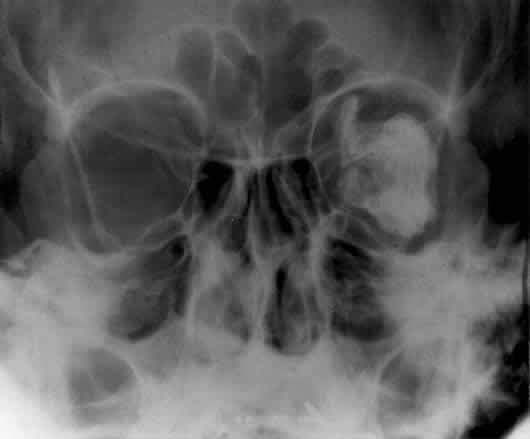

CALDWELL PROJECTION

In 1918 the evaluation of the frontal and ethmoid sinuses prompted Caldwell9 to describe a projection (Fig. 3) that eliminates the superimposition of the sphenoid bone on these paranasal sinuses. The patient is positioned with both the nose and forehead against the x-ray cassette while the x-ray beam is directed downward 15 degrees to 23 degrees to the canthomeatal line.5,6,9 This orientation also projects the petrous bones inferior to the orbit, thus avoiding obscuration of the orbital structures. As in the Waters view, the Caldwell view is a posterior-anterior projection. This excellent view of the frontal and ethmoid sinuses also allows good visualization of the orbital rims, greater and lesser sphenoid wings, lacrimal gland fossa, medial orbital wall, and both the superior and inferior orbital fissures.10 The innominate line is prominent in this view and represents the depression on the temporal surface of the greater wing of the sphenoid bone where it forms the medial wall of the temporal fossa or lateral wall of the orbit. This innominate line can be straight, end with a medial right angle turn, or continue inferiorly to form the outline of the pterygoid plate.8 A lack of continuity of the innominate line suggests a fracture of the lateral orbital wall.

Fig. 3. A. Schematic showing positioning for a Caldwell projection. (CM, canthomeatal line; CR, central ray) B. Radiograph of a Caldwell projection. The petrous ridge is positioned at the orbital floor. Detail of the orbital floor and maxillary sinus is blocked. C. The radiograph is taken at a steeper angle so the petrous ridge is now positioned lower within the maxillary antrum. (a, frontal sinus; b, innominate line; c, inferior orbital rim; d, posterior orbital floor; e, superior orbital fissure; f, greater wing of sphenoid;g, ethmoid sinus; h, medial orbital wall; i, petrous ridge; j, zygomatic-frontal suture; k, foramen rotundum) (A; Rao VM, Gonzalez CF: Plain film radiography and polytomography of the orbit. In Gonzalez CF, Becker MH, Flanagan JC [eds]: Diagnostic Imaging in Ophthalmology, pp 1–7. New York, Springer Verlag, 1986)